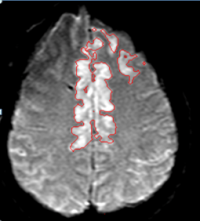

3D Segmentations of Brain Tumor, Necrosis and Edema

Guo X, Schwartz LH and Zhao B, Semi-automated Segmentation of Multimodal Brain Tumor Using Active Contours. Proceedings of MICCAI 2013, BRATS: 17-30.

Chow DS, Qi J, Guo X, Miloushev VZ, Iwamoto FM, Bruce JN, Lassman AB, Schwartz LH, Lignelli A, Zhao B, Filippi CG. Semi-automated volumetric measurement on post contrast MR imaging for analysis of recurrent and residual disease in glioblastoma multiforme. AJNR Am J Neuroradiol. 2014; 35(3):498-503.